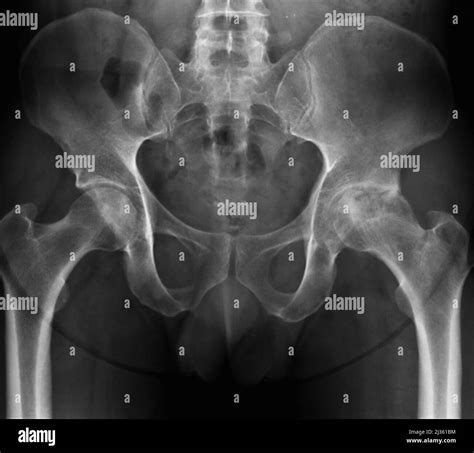

So, how do doctors figure out if you’ve got osteoarthritis? It’s usually a combination of things. First off, they’ll want to hear your story – that’s the medical history . They’ll ask about your symptoms, when they started, what makes them better or worse, and if you have any past injuries or family history of arthritis. Then comes the physical examination . Your doctor will look at the affected joint for swelling, tenderness, and listen for any grating sounds (crepitus) when you move it. They’ll also check your range of motion and assess your muscle strength around the joint. Imaging tests are super important for confirming the diagnosis and seeing how much damage has been done. X-rays are the most common. They can show you the extent of cartilage loss, bone spurs, and changes in the joint space. Sometimes, if X-rays aren’t clear enough or if your doctor suspects other issues, they might order an MRI (magnetic resonance imaging) scan. MRIs provide more detailed images of soft tissues, like cartilage, tendons, and ligaments, giving a clearer picture of the joint’s condition. In some cases, though less common for initial diagnosis, a joint fluid analysis might be done. This involves using a needle to withdraw fluid from the affected joint. The fluid is then tested to rule out other types of arthritis, like gout or rheumatoid arthritis, and to check for signs of infection. The combination of your symptoms, a physical exam, and imaging results usually allows your doctor to confidently diagnose osteoarthritis and start planning the best course of treatment for you. It’s all about gathering clues to understand what’s going on inside your joint.